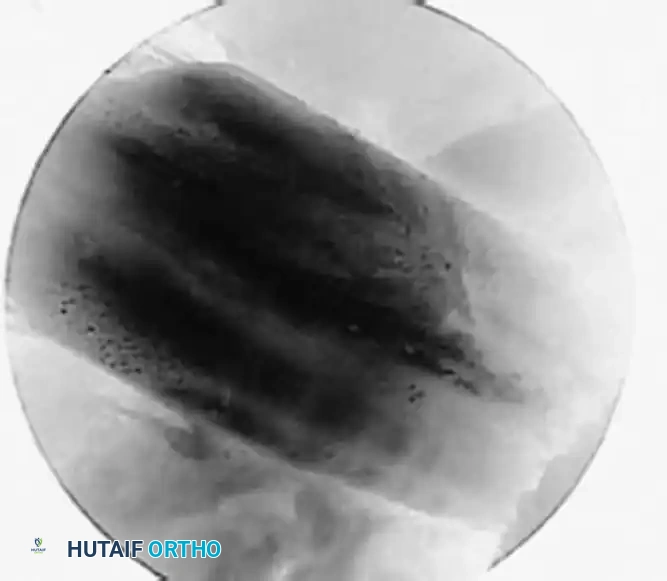

• Use a 15-degree upbiting low-profi le basket to make removal of a posterior horn tear easier.

• Carry the resection out through the ipsilateral portal, trimming back to a stable contoured peripheral rim (Fig. 48-20).

A B C

Fig. 48-20 Technique for longitudinal incomplete intrameniscal tears. A, Probing longitudinal intrameniscal incomplete inferior surface tear. B, Fragment is removed bit by bit with basket forceps. C, Rim is smoothed and contoured with motorized trimmer.